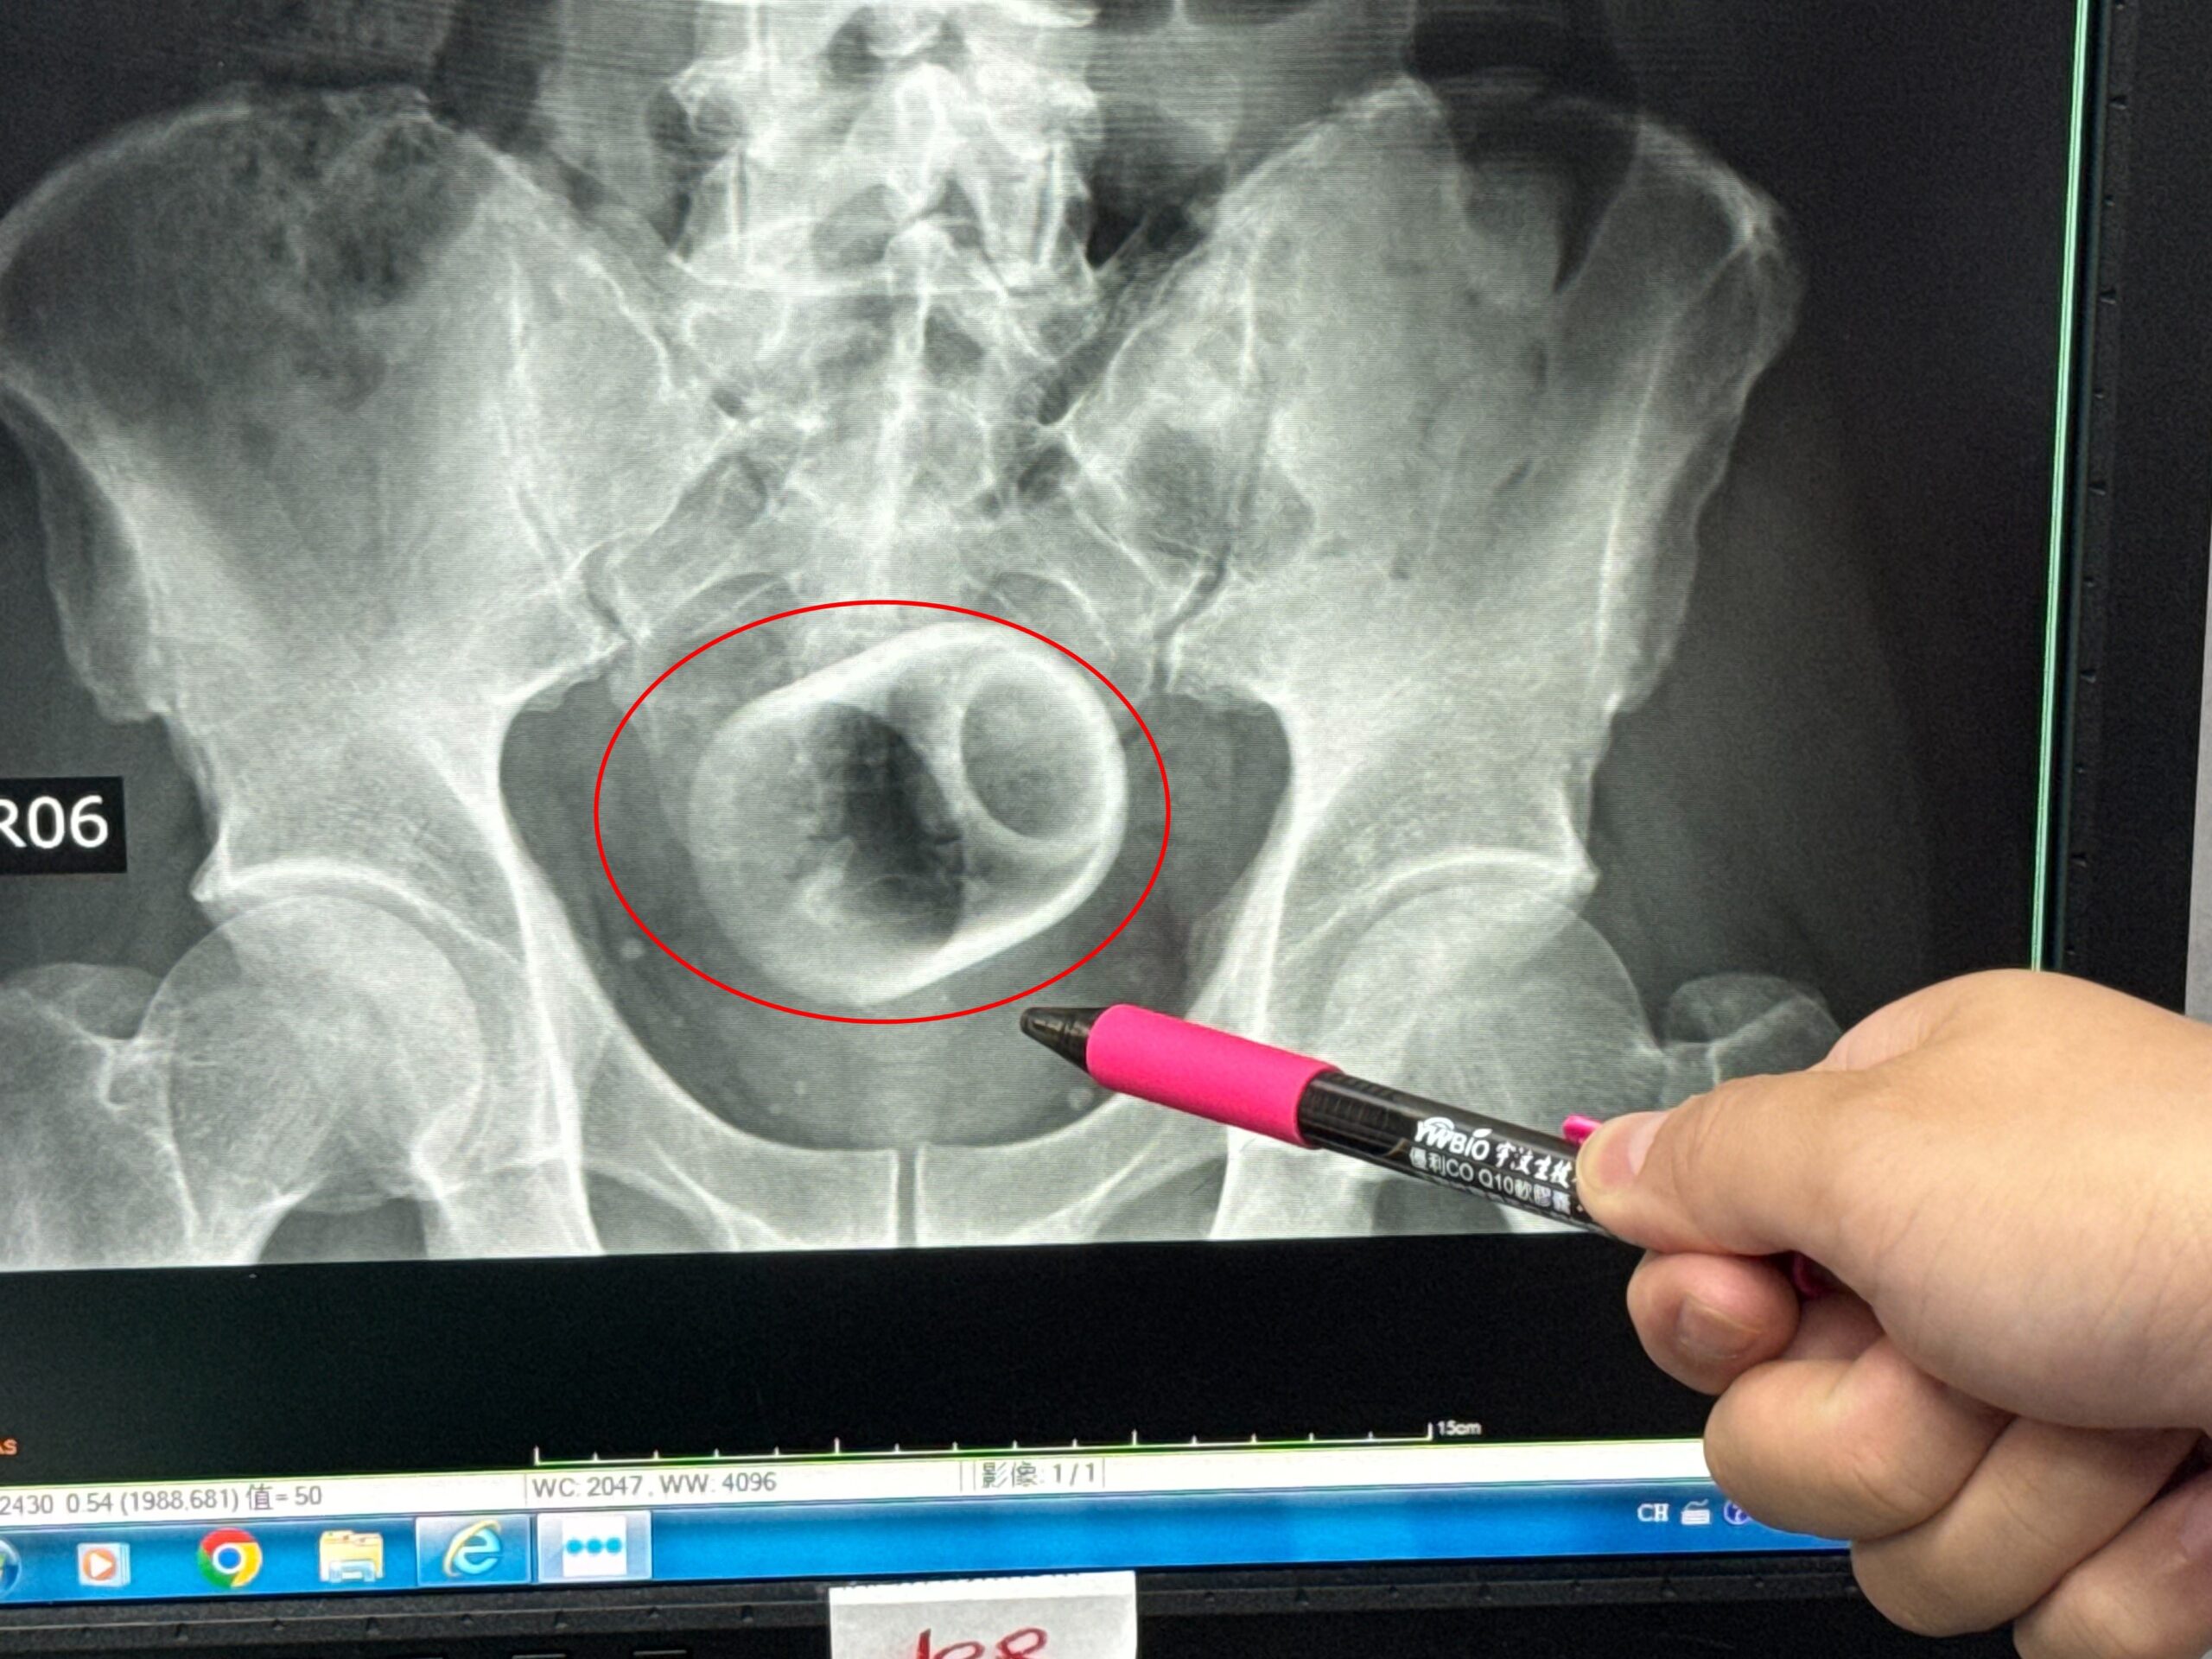

Una radiografía reveló que dentro de él había una taza de cerámica.

Los médicos, que medían unos 6 cm de ancho y 8 cm de alto, intentaron retirar la pieza de vajilla.

Si bien utilizaron instrumentos para intentar sacarlo, la superficie lisa de la copa les dificultaba agarrarla.

Los intentos de utilizar la laparoscopia también fracasaron porque los médicos temían que demasiada fuerza pudiera romper la copa.